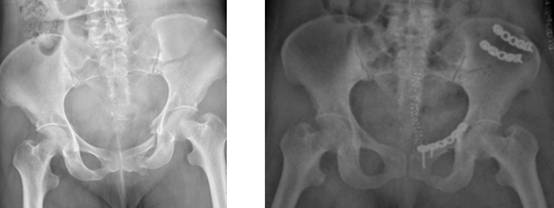

术前术后X光影像片

患者病情危重,多发性骨折带来极大挑战。据了解,该患者因高处坠落伤,导致骨盆骨折、腰椎骨折、跟骨骨折、胫骨平台骨折、桡骨远端骨折等多部位严重损伤,病情复杂且危重,于9月30日被收治入院。面对如此严峻的挑战,在科室主任李宝权及副主任李烁的带领下,骨外科四病区医疗团队迅速响应,立即完善相关检查,并给予了积极的支持治疗。

“对于这类严重的多发性创伤,我们遵循的是损伤控制原则。”李烁副主任介绍。团队为此制定了缜密的“分期手术、优先处理关键部位”治疗方案。其中,骨盆骨折的处理是核心,也是最大的难点。骨盆结构复杂,紧邻重要血管、神经及脏器,手术难度大、风险极高,被视为骨科领域最具挑战性的损伤之一。这类手术通常需等待患者身体状况稳定后,在伤后一周左右的最佳时间窗进行。